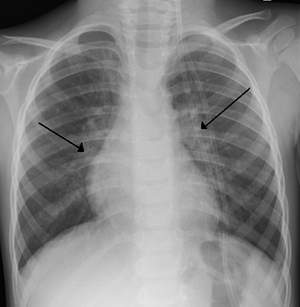

기관지염이 오래되게 되면 기관지가 늘어난 상태를 유지하게되어, 기관지확장증 이 생길 수도 있습니다. 넓어진 폐포를 생각하면, 기능이 많이 떨어지게 되고, 가래가 만성적으로 늘게되고 가래도 많이 늘게되는 것 입니다. 증상은 주로 기침과 누런가래가 나오게 됩니다. 폐는 한번 망가지면, 그전의 기능으로 돌아오기 힘들기 때문에 초기에 관리를 잘해주어야합니다.

마지막으로, 폐 및 호흡관련된 기관의 해부학적인 모습을 공유하고 글을 맞치도록 하겠습니다.